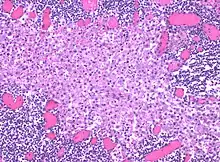

In medicine, histiocytosis is an excessive number of histiocytes[1] (tissue macrophages), and the term is also often used to refer to a group of rare diseases which share this sign as a characteristic. Occasionally and confusingly, the term histiocytosis is sometimes used to refer to individual diseases.

Histiocytosis is a rare disease, thus its diagnosis may be challenging. A variety of tests may be used, including:[5]